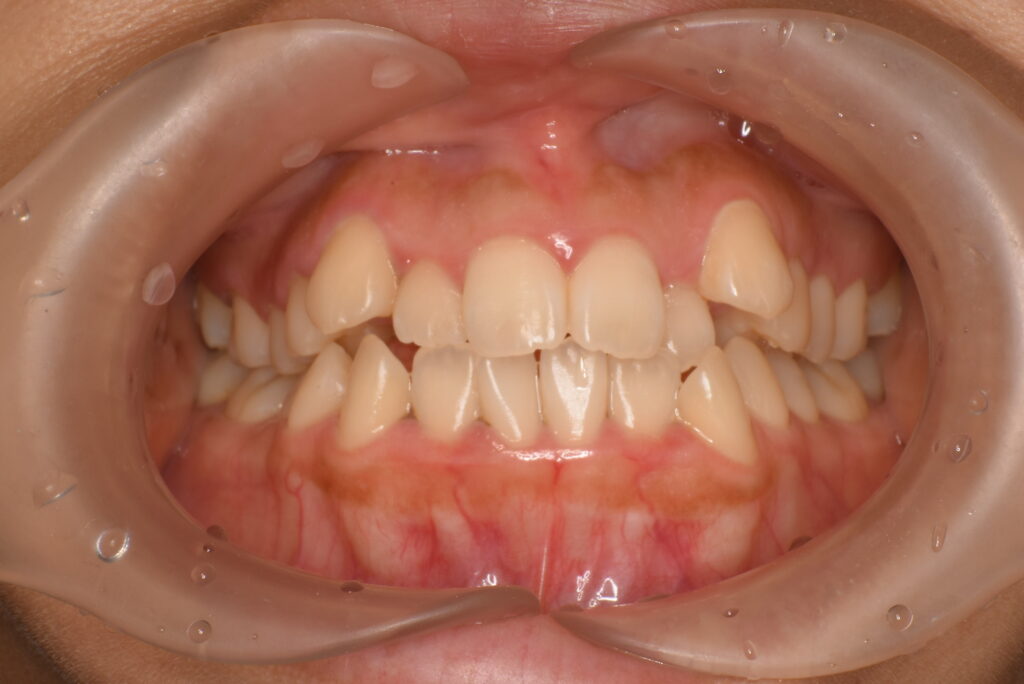

- BEFORE

| 治療内容 | 患者様は、歯のガタつきやデコボコした不揃いな歯並び、歯に汚れがつきやすく磨きにくいことを主訴に来院されました。10年以上ぶりの歯科受診で、歯ぐきからの出血(歯肉炎:歯肉病の初期症状)が多く見られたため、インビザライン治療に入る前にブラッシング指導(TBI)や歯周病治療を行い、口腔内環境を整えてから矯正治療を開始しました。 治療開始前には左上の歯の虫歯治療を行い、その後インビザライン治療をスタートしました。抜歯は行わず、非抜歯矯正で歯列を整える方針とし、歯の移動に必要なスペースを確保するために IPR を行いながら治療を進めました。インビザライン治療と並行して歯周病治療も継続し、歯列の改善と口腔内の健康維持の両方を図りました。 |